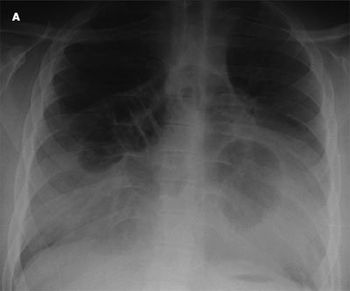

A 5-year-old girl was brought to the emergency department after she was injured during a drive-by shooting. She had 5 small entry wounds: 2 in the arm, 2 in the buttocks, and 1 in the left torso. Radiographs confirmed that a piece of pellet had entered her upper torso but was not in the lung or causing any problem.